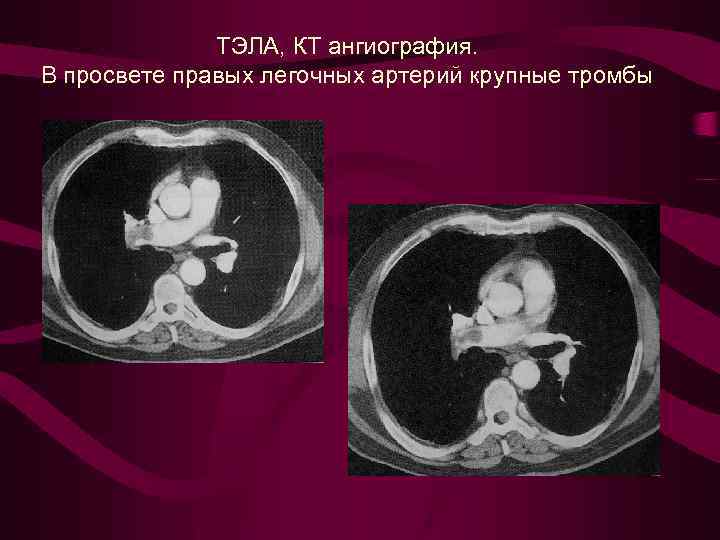

ТЭЛА, КТ ангиография. В просвете правых легочных артерий крупные тромбы

ТЭЛА, КТ ангиография. В просвете правых легочных артерий крупные тромбы